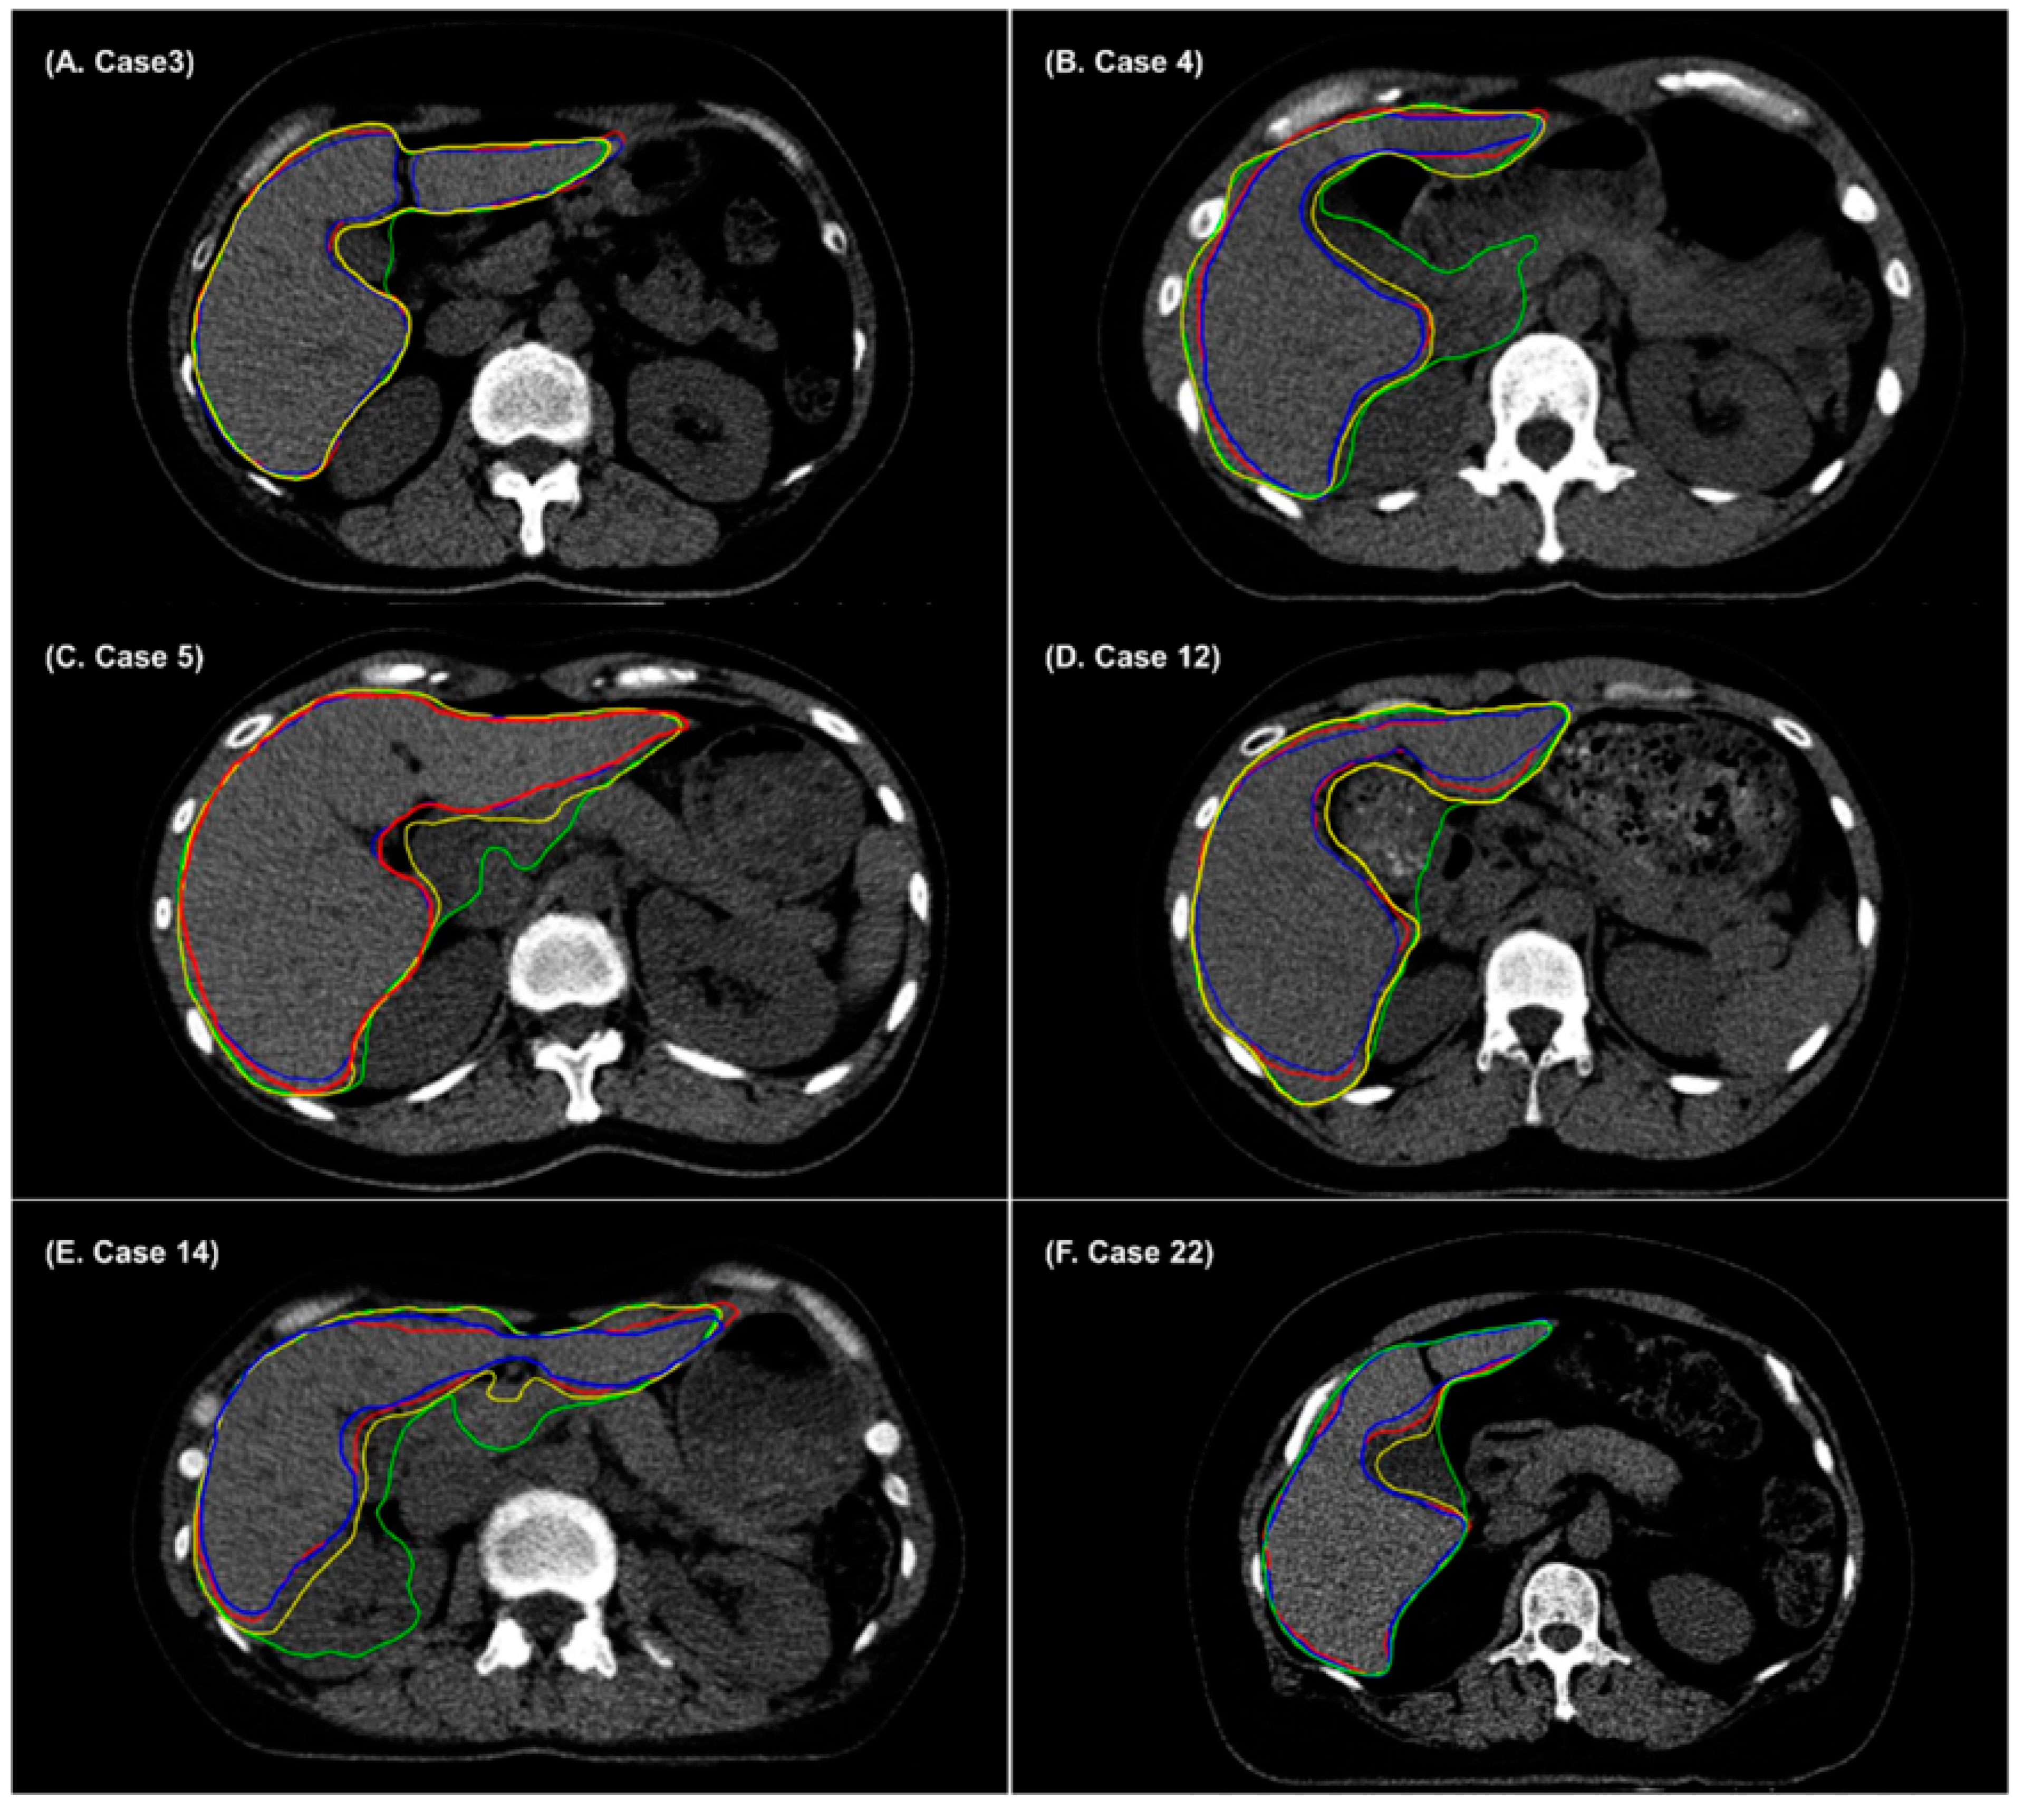

- Chung, S.Y.; Chang, J.S.; Choi, M.S.; Chang, Y.; Choi, B.S.; Chun, J.; Keum, K.C.; Kim, J.S.; Kim, Y.B. Clinical feasibility of deep learning-based auto-segmentation of target volumes and organs-at-risk in breast cancer patients after breast-conserving surgery. Radiat. Oncol. 2021, 16, 1–10. [Google Scholar] [CrossRef] [PubMed]

- Choi, M.S.; Choi, B.S.; Chung, S.Y.; Kim, N.; Chun, J.; Kim, Y.B.; Chang, J.S.; Kim, J.S. Clinical evaluation of atlas-and deep learning-based automatic segmentation of multiple organs and clinical target volumes for breast cancer. Radiother. Oncol. 2020, 153, 139–145. [Google Scholar] [CrossRef]